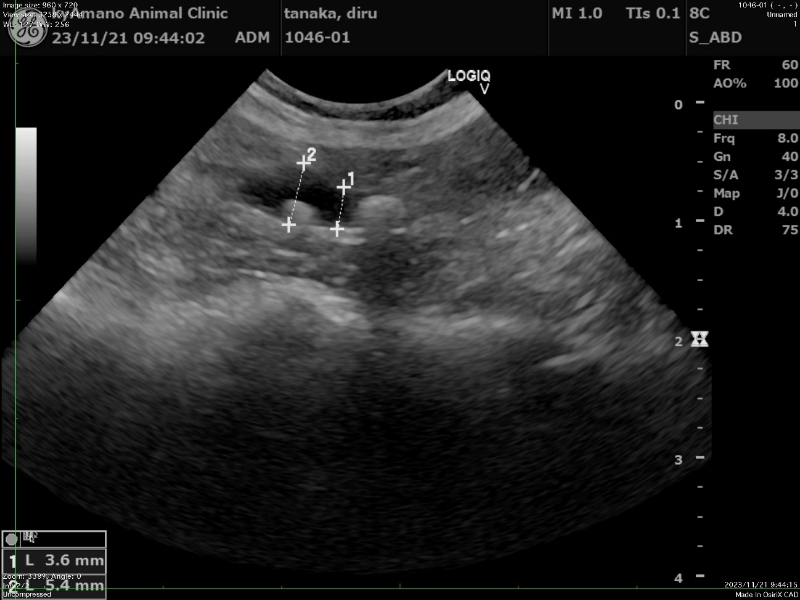

Step03検査

症状や状態に応じて、血液検査、尿検査、超音波検査、血圧測定などをご提案させていただきます。尿道閉塞などで重症の場合、救命行為として最小限の説明の後、状態を安定させるために一部の検査や処置を優先して実施させていただく場合もございます。